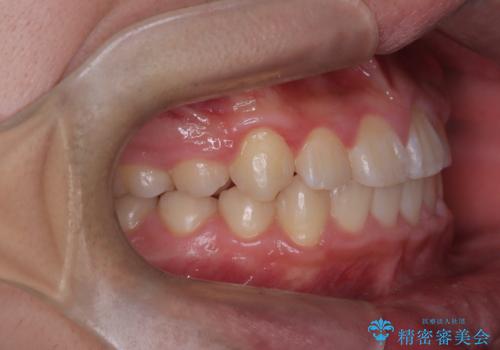

八重歯・歯並びのデコボコとディープバイトを改善した抜歯ワイヤー矯正症例

八重歯などの歯列のデコボコが綺麗に改善され、患者様にも大変喜んでいただけました。また、咬み合わせが深い「ディープバイト」も併せて改善し、見た目だけでなく機能面でもバランスの取れた咬合を獲得しています。